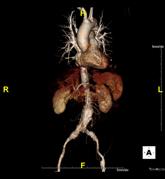

Das Klinikum Ludwigshafen verfügt über einen Kardio-CT der neuesten Generation: Das 128-Zeilen-Gerät ermöglicht eine äußerst präzise Untersuchungsmethode zur Darstellung der Herzkranzgefäße des schlagenden Herzens.

Die koronare Herzerkrankung (KHK) ist eine der häufigsten Erkrankungen in der westlichen Welt. Bei dieser Erkrankung führen Kalkablagerungen an der Gefäßwand (Arteriosklerose) zur Verengung des betroffenen Gefäßes. Diese Engstellen (Stenosen) vermindern die Blutversorgung des Herzmuskels. Kommt es mit dem Fortschreiten der KHK zum Gefäßverschluss, entsteht ein Herzinfarkt.

Die Computertomografie des Herzens (Kardio-CT) ist eine Methode, die frühen Stadien der KHK zu erkennen, bzw. eine KHK mit an Sicherheit grenzender Wahrscheinlichkeit ausschließen zu können.

Prinzipiell ist die Kardio-CT eine Computertomografie (CT), also eine Röntgenuntersuchung, bei der die Röntgenröhre spiralartig um den Patient rotiert. Das Besondere ist die enorme Leistungsfähigkeit der CT, bei der mehrere, sehr dünne Schichten pro Umdrehung gleichzeitig aufgenommen werden.

In Ludwigshafen verwenden wir einen CT der neuesten Generation der Firma Siemens, mit dem wir 128 Schichten pro Umdrehung aufnehmen. Auf diese Weise lässt sich das gesamte Herz mit nur vier bis fünf Umdrehungen erfassen. Für Sie bedeutet das, dass wir Ihre Herzkranzgefäße in der derzeit bestmöglichen Auflösung und mit geringst möglicher Strahlenbelastung darstellen können.